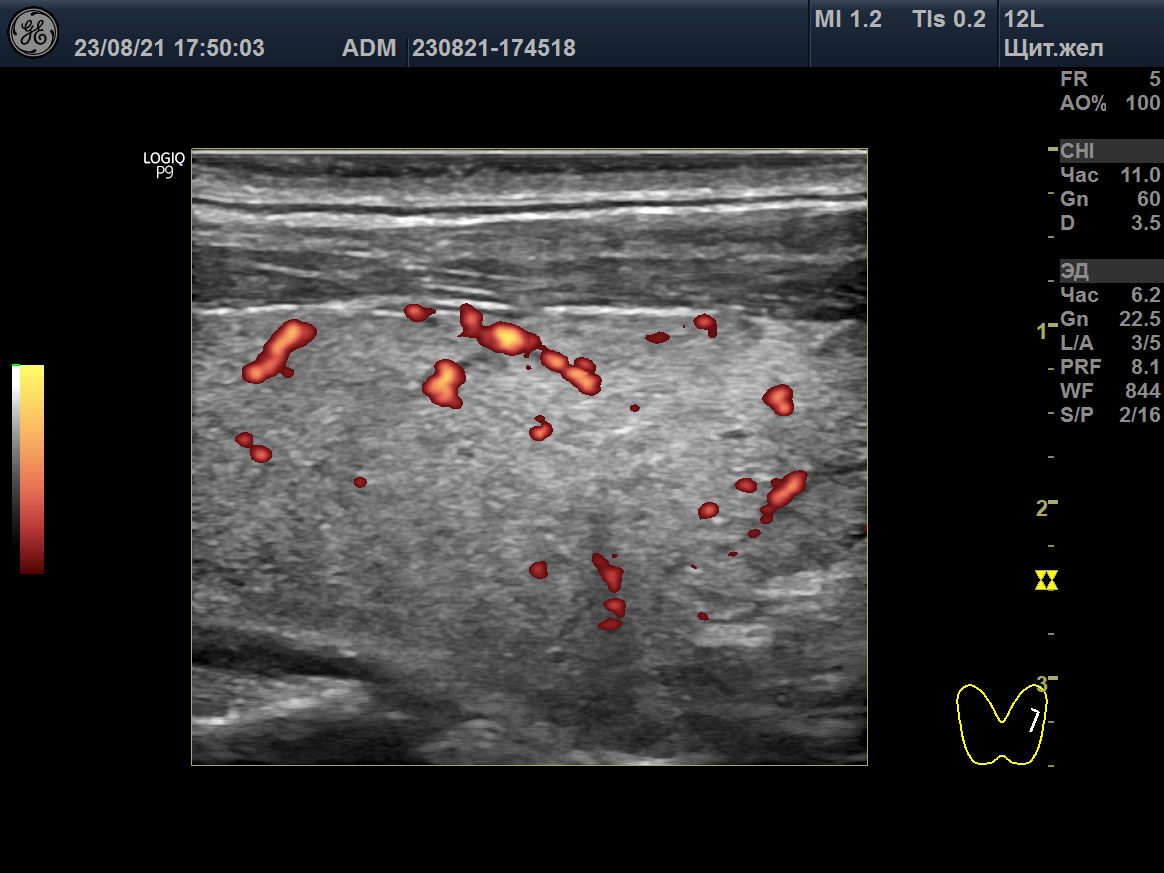

Изображения щитовидной железы пациента в режиме Допплера. A, B, C ― до лечения (15 мая 2018), и D, E, F после лечения (23 августа 2021). A, D ― поперечная проекция левой доли. B, E ― продольная проекция левой доли. C, F ― SPV STA слева.

Одновременно с восстановительной динамикой гормонального и иммунного обмена в отношении щитовидной железы, УЗИ также показывало значительное улучшение (таблица 2). Через 10 месяцев (13 февраля 2019) было выявлено изменение объёма железы до 30,4 мл, уменьшение отёка стромы и снижение интенсивности кровотока. SPV STA стали 38 cm/sec справа и 47 cm/sec слева.

Вместе с тем, в августе 2021, при нормальном гормональном обмене и АТ-рТТГ 0,3 Ед/л (<1,5), объём щитовидной железы остался прежним (30,4 мл), у дорсального края в обеих долях сохранялись некоторые признаки отёка стромы, интенсивность кровотока с двух сторон в очень малой мере была усилена, улучшилась SPV STA – 27 cm/sec справа и 39 cm/sec слева (таблица 2; рисунок: D, E, F). В декабре 2022 ультразвук показал подобные признаки с незначительным улучшением: объем щитовидной 24 мл и преобладание изоэхогенной паренхимы.